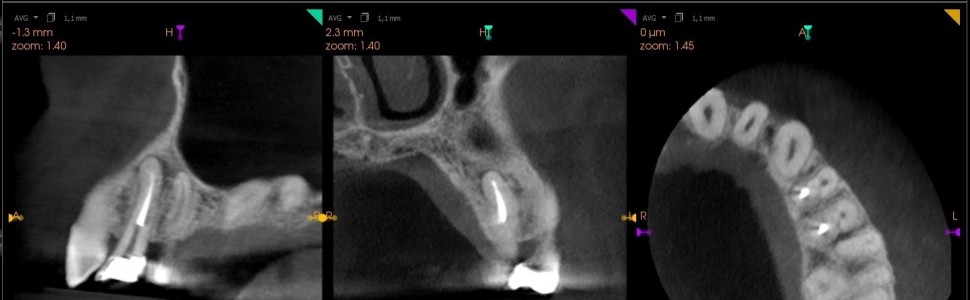

Artykuł przedstawia leczenie przewlekłego, ropnego zapalenia tkanek okołowierzchołkowych okolicy lewych przedtrzonowców szczęki u 53-letniego mężczyzny, zakończone sukcesem. Plan leczenia, oparty na diagnostyce tomograficznej oraz badaniu klinicznym obejmował leczenie niechirurgiczne, z następowym ewentualnym zabiegiem z zakresu mikrochirurgii endodontycznej. Powtórne leczenie endodontyczne zgodne z protokołami współczesnej stomatologii, doprowadziło do całkowitego wygojenia się zmian zapalnych, a prawidłowa odbudowa zębów odegrała znaczącą rolę w ich utrzymaniu.

A case report shows the successful management of left maxillary premolars with a chronic periodontitis in a 53-year- old male. The treatment plan, based on a Cone Beam Computed Tomography and the clinical examination, included non-surgical treatment, possibly followed by microsurgical endodontic treatment. The endodontic re-treatment, carried out in accordance with the principles of modern dentistry, led to the full healing of inflammatory lesions. The correct reconstruction played a major role in improving the prognosis of the tooth.